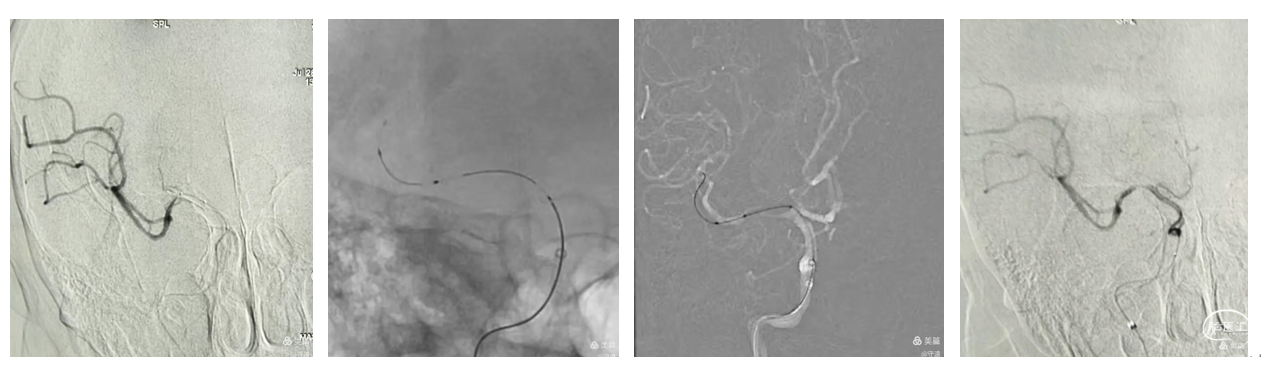

颅内支持导管到达C5段由于血管迂曲成环难以上行。微导丝在C6段形成回头弯顺利到达M2段,Fastunnel输送型球囊扩张导管到达M分叉部。撤出微导丝,微造影显示Ml1分叉以远血流通畅,真实球囊扩张导管在M1段真腔内。

再次球囊扩张:再次将球囊扩张导管置于M1段,在6个大气压(命名压)下扩张导管,泄压后回撤导管造影,右侧大脑中动脉全程血流通畅达3级,远端未见明确血栓逃逸。M1段毛糙,考虑残余狭窄约40%。术中推注替罗非班10mL,撤出导管系统造影大脑中动脉全程血流通畅。